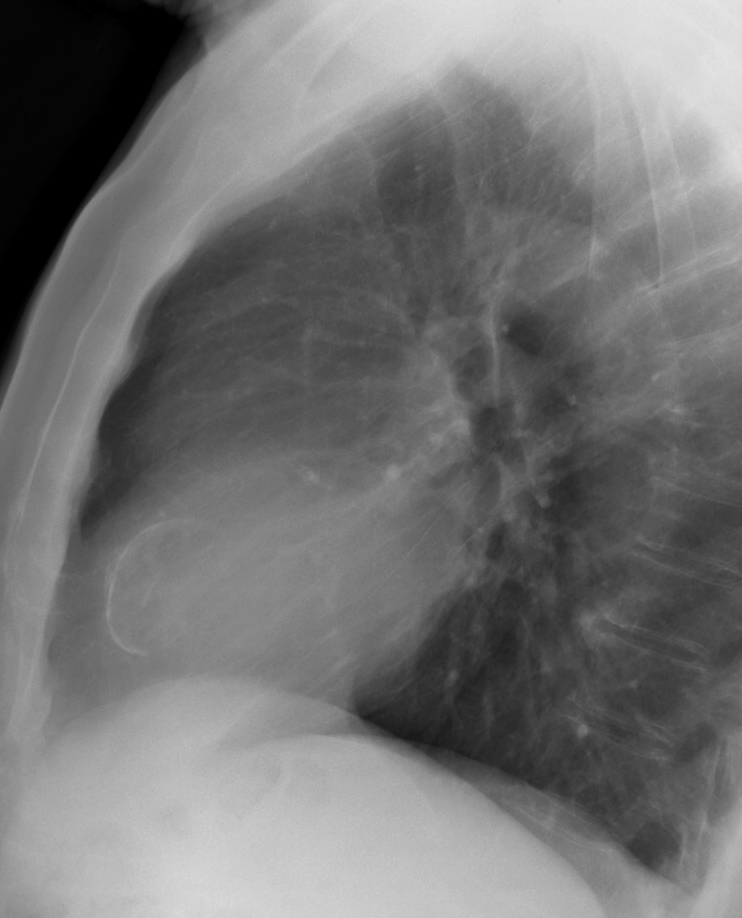

Cardiac

Other

LV calcific lat